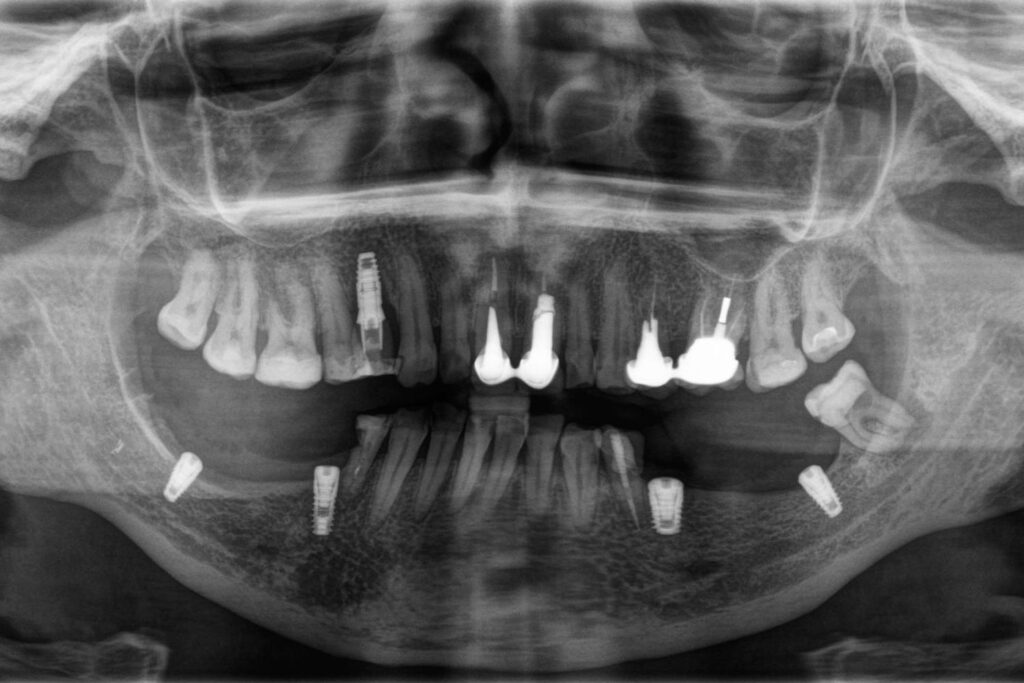

На КТ-исследовании мы обнаружили уменьшение объема кости и то, что в дальних отделах нижней челюсти расстояние до нижнечелюстного нерва составляет 5-6 мм. Поскольку была задача провести имплантацию и протезирование с минимальными финансовыми затратами, было принято решение сделать функциональную работу (без костной пластики).

Сложность работы заключалась в том, что нужно было расположить имплантат таким образом, чтобы он проходил по передней стенке нижнечелюстного нерва, не задев его. Такую работу можно сделать только с помощью специального КТ-аппарата и специализированных программ. После планирования имплантации и изготовления шаблона мы смогли установить импланты так, как мы хотели (не задев нерв) и получили прогнозируемо хороший результат.